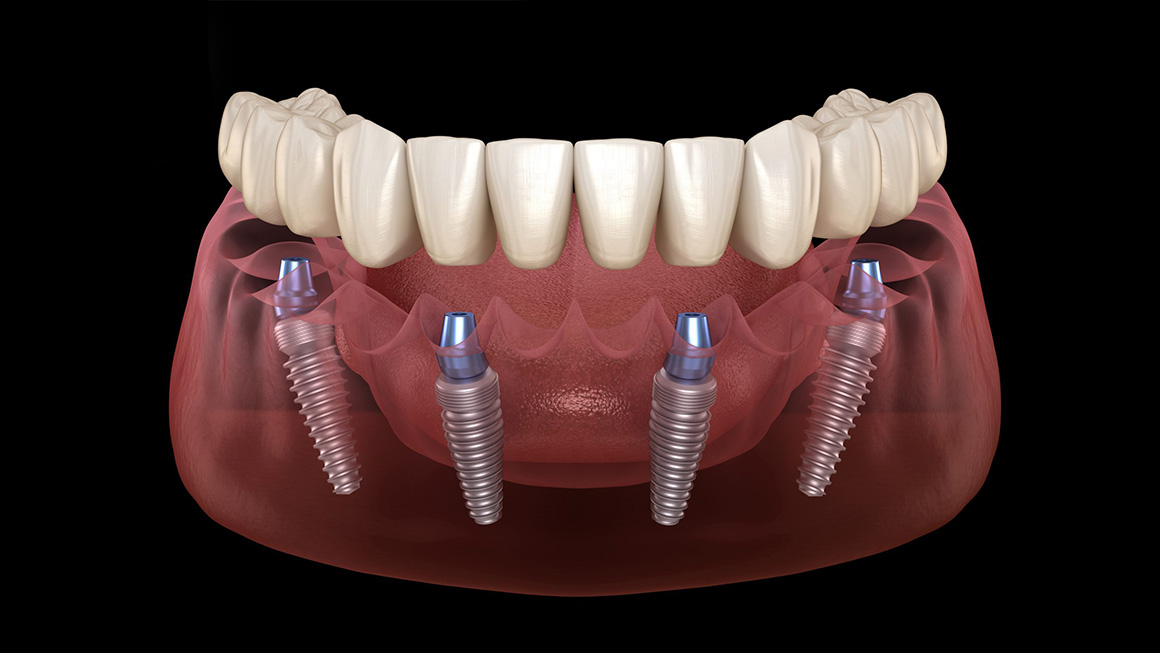

All-on-4 Dental Implants

Start from £ 3000

Timescale 7 days

Digital Precision and Specialization: Because Antalya is a global hub for dental tourism, our surgeons perform high-complexity restorations, such as “All-on-4” and full-mouth rehabilitations, at a much higher frequency than the average local dentist in London or New York. We utilize 3D Tomography and digital smile design to create a precise “blueprint” of your jaw, ensuring a level of surgical accuracy that minimizes trauma and accelerates biological healing.

Dental implants in Antalya represent the perfect intersection of advanced medical technology and world-class hospitality. At Hair Legends, we define a dental implant not just as a replacement tooth, but as a sophisticated architectural restoration of your facial structure. This procedure involves placing a biocompatible titanium or ceramic post into the jawbone, which acts as a permanent root to support a handcrafted crown.

Choosing Antalya for this transformation allows you to access elite tier Swiss and German implant systems at a fraction of Western costs, managed within a boutique ecosystem. Our approach focuses on biological healing; by combining surgical mastery with premium logistics and secluded luxury stays, we ensure your implants integrate seamlessly. In Antalya, a dental implant is more than a clinical treatment it is a stress-free journey toward a permanent, natural, and legendary smile.